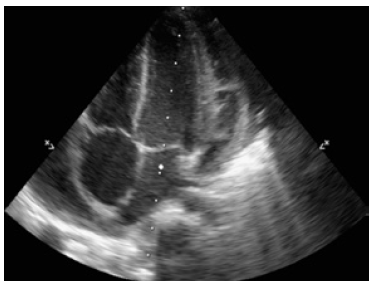

In addition, an echocardiogram showed global pericardial effusion and the presence of thick membranes between the visceral and parietal pericardium, without signs of cardiac tamponade, adequate ventricular function, ventricular ejection fraction of 77% and central venous pressure of 8-10mmHg, without signs of pulmonary hypertension (Figure 3).

Echocardiogram with apical four chamber view (A, B) and coronal axial plane (C).

Figure 3: Echocardiogram with apical four chamber view (A, B) and coronal axial plane (C).

Source: Own elaboration based on the data obtained in the study.

The echocardiogram is the diagnostic method of choice to clarify radiological findings. 2,3 In this case, it showed a global pericardial effusion associated with the presence of thick membranes between the visceral and parietal pericardium, without cardiac tamponade, systolic-diastolic function involvement or alterations in the myocardium. Computed tomography (CT) is indicated when emergency echocardiogram is not available and when inconclusive echocardiographic results, poor response to treatment, atypical presentation, penetrating lesion, suspicion of neoplasms and pulmonary infections or mediastinitis are observed. 13 This patient did not require chest CT because of his rapid improvement, which reduced the possibility of complications.